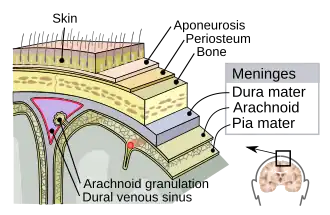

| Meninges of the central nervous system: dura mater, arachnoid mater, and pia mater. | |

The meninges comprise three membranes that, together with the cerebrospinal fluid, enclose and protect the brain and spinal cord (the central nervous system). The pia mater is a delicate impermeable membrane that firmly adheres to the surface of the brain, following all the minor contours. The arachnoid mater (so named because of its spider-web-like appearance) is a loosely fitting sac on top of the pia mater. The subarachnoid space separates the arachnoid and pia mater membranes and is filled with cerebrospinal fluid. The outermost membrane, the dura mater, is a thick, durable membrane that is attached to both the arachnoid membrane and the skull.